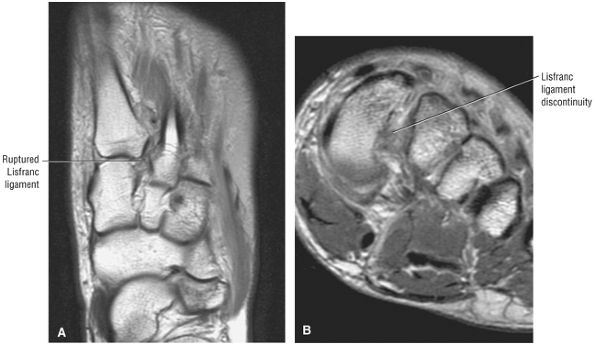

FIGURE 5.27 ● Axial anatomy of the ankle and foot. (A) The flexor digitorum longus, flexor hallucis longus, peroneus brevis, soleus, and extensor digitorum muscles are examined at this level for strain, tears, or fatty atrophy that may suggest denervation. (B) The tibialis anterior, extensor hallucis longus, and extensor digitorum longus tendons are examined on every ankle MR examination. Extensor tendon pathology is frequently overlooked if these tendons are not included as part of the ankle checklist. (C) Tears and sprains of the anterior syndesmotic ligament are a frequent cause of persistent ankle pain following ankle sprain. The syndesmotic ligaments are thick, tough ligaments that are important ankle stabilizers, and delayed diagnosis of syndesmotic tears may result in significant degenerative arthrosis at the tibiotalar joint due to the resulting ankle instability. The syndesmotic ligaments course obliquely inferiorly from the tibia to the fibula and are not usually visualized in their entirety on a single axial image; rather, their course is followed on at least two or three successive axial images. (D) The peripheral margin of the peroneal tendons and tibialis posterior tendon should normally never extend beyond the peripheral margins of the lateral and medial malleoli, respectively. Tendon subluxation around the posterior corner of either malleolus is indicative of a tear of the overlying flexor retinaculum (medially) or peroneal retinaculum (laterally). When the retinacula are torn, the tendon is free to intermittently sublux or dislocate, leading to tendon degeneration, pain, and tendon dysfunction. (E) Suspected osteochondral lesions of the talar dome are visualized and further characterized on axial images through the top of the talar dome. (F) The peroneus brevis tendon may normally appear somewhat flattened. However, as the tendon degenerates, it becomes U-shaped and drapes around the anterior aspect of the peroneus longus and becomes impinged between the peroneus longus tendon and the lateral malleolus. With further degeneration, the peroneus brevis may split or completely rupture. (G) Evidence of anterior talofibular ligament injury is visualized on the majority of MR ankle examinations and appears as thickening, intermediate signal with ill-defined fibers, or attenuation of the ligament. This is commonly asymptomatic. (H) Because the flexor hallucis longus tendon sheath communicates with the tibiotalar joint, fluid may normally be present within the tendon sheath in proportion to the amount of fluid in the tibiotalar joint. If there is fluid within the tendon sheath out of proportion to that seen in the tibiotalar joint, tenosynovitis is most likely present. The finding of flexor hallucis longus tenosynovitis should prompt a search for an os trigonum, as impingement of the flexor hallucis longus tendon between an os trigonum and the posterior tibial plafond is a common cause for FHL tenosynovitis. (I) The calcaneofibular ligament (CFL) passes anterior and medial to the peroneal tendons. On the image at which the CFL passes directly medial to the peroneus brevis tendon, the appearance of the peroneus brevis and the CFL side by side is occasionally mistaken for a split peroneus brevis tendon. (J) Dilated posterior tibial veins within the tarsal tunnel occasionally compresses the tibial nerve. In the setting of clinical suspicion for tarsal tunnel syndrome or if there is evidence of muscle denervation on MR images, the size of the posterior tibial veins should be described. (K) The spring ligament is identified at this axial image location, extending from the anteromedial calcaneus to the posteromedial navicular. Tears of the spring ligament may result in medial instability and hindfoot valgus. (L) The posterior tibialis tendon (PTT) may normally become thickened and fan-like as it passes posterior to its navicular insertion (prior to also inserting on the cuneiforms and the base of the second through fourth metatarsals). In the absence of other findings, the thickening of the PTT at this level should not be mistaken for focal tendinosis. (M) On inferior images through the ankle, Lisfranc's ligament is occasionally included in the FOV. Lisfranc's ligament extends from the medial cuneiform to the base of the second metatarsal. If Lisfranc's ligament is included in the FOV, the status of the ligament should be described, as undiagnosed Lisfranc ligament tears can lead to debilitating midfoot arthrosis. (N) As the medial and lateral tendons turn from their vertical course to a horizontal course along the plantar aspect of the foot, the tendons may demonstrate a magic-angle artifact, causing the tendons to appear gray on short-TE images, mimicking tendinosis. Correlation with images using longer TE values is advised in such situations.